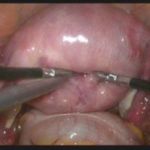

子宫腺肌症是一种子宫内膜异位到子宫肌层而导致的子宫肌腺病,多数医院采取切子宫,北京安太医院进行3D腔镜下保宫治疗,不论有无贫血,有无生育要求,一律保宫,不开腹,不切子宫,一次清除病灶不反复,案例分享:河北保宫患者子宫腺肌症治疗真实感受。